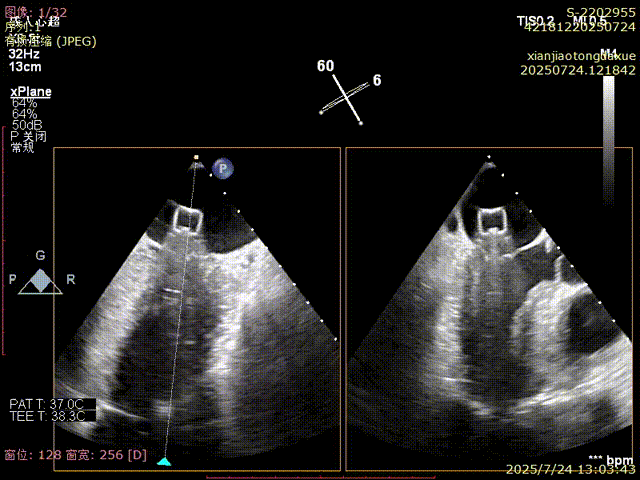

左房打开上夹

捕获瓣叶并进行夹合

确认夹合位置及效果

3D确认夹合位置